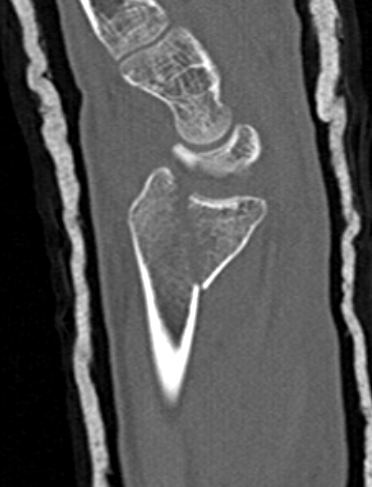

Volar rim fractures

Definition

Very distal fractures

Need distal plates

Low profile plates to protect flexor tendons

Technique

Plate sits distal to watershed line

- variable angle screws

- sit in subchondral bone

- can cause flexor tendon irritation and may need removal

Outcomes

Lari et al Eur J Orthop Surg Traumatol 2023

- systematic review of surgical treatment of volar rim fractures

- 26 studies and 600 patients

- implant removal 22%

- flexor tendon irritation 6%